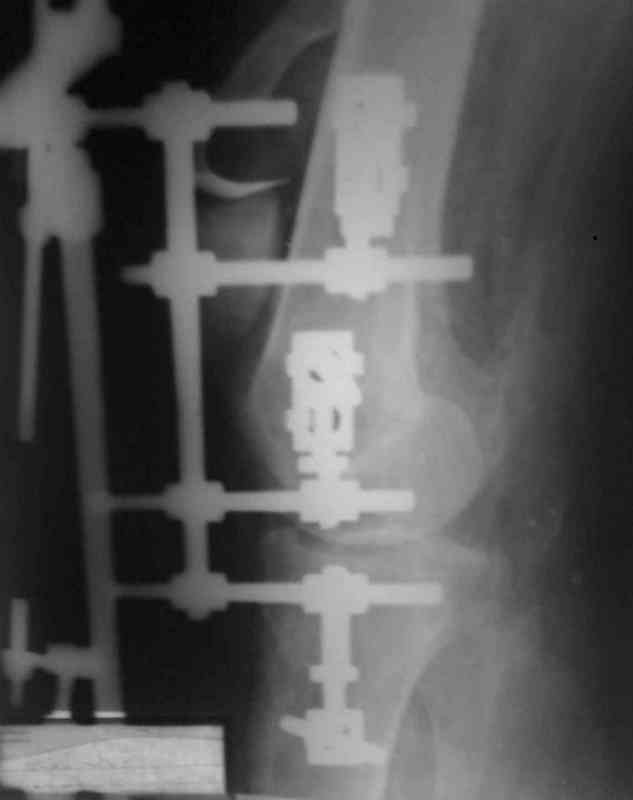

Аппарат внешней фиксации удаляется в 6-7 недель,

предпочтительно под общим обезболиванием, во время

удаления проверяется стабильность и амплитуда движения в коленном суставе с редрессацией.

При пользовании стержневых наружных фиксаторов,

надо придерживаться правила проведения стержней подальше от зоны, на бедре лучше накладывать стержни косо передне-латерально, между брюшками прямой и vastus lateralis, а на голени по передне-медиальной поверхности большеберцовой кости, где отсутствует мышцы, иначе

восстановление движения в суставе тяжелее из-за

прошитых мышц спицами или стержнями аппарата.

Снимки прошлых публикации из моего Power point